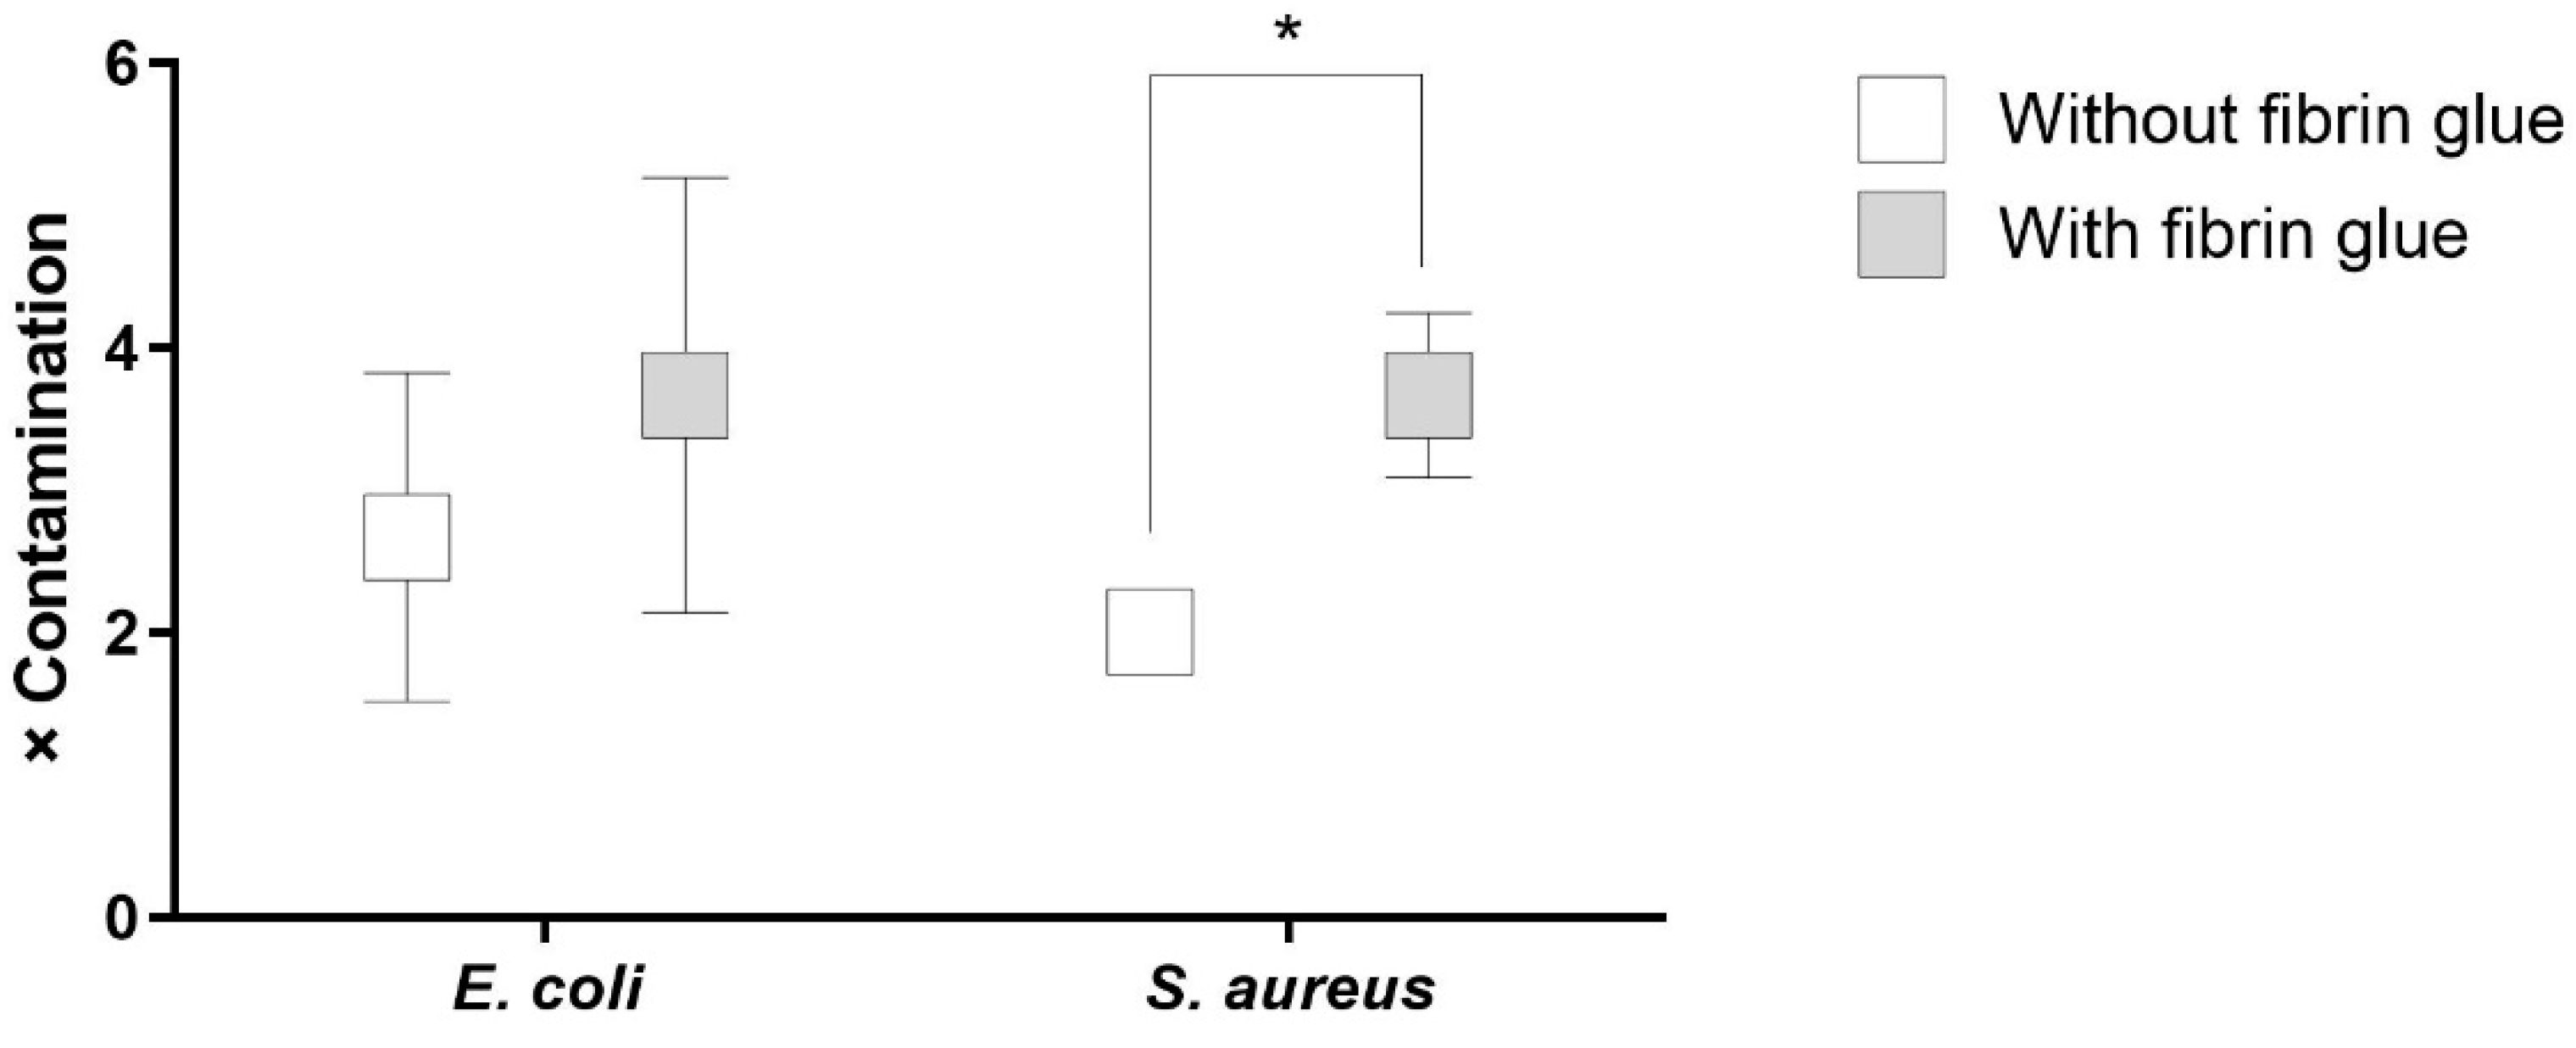

2.2.2. Coated Grafts

2.4. Antibacterial Activity against Recurrent Contamination